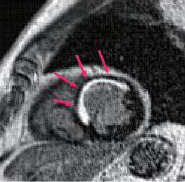

Cardiac MRI

遅延造影MRIによる心筋梗塞の診断

左室短軸画像、前壁中隔梗塞

また最新鋭の装置を用いて心臓MRI検査も行っています。全体の撮影自体は40分から1 時間とやや長いですが、1 回の検査で心臓の形態評価、心機能評価、心筋性状の評価が行えます。心筋梗塞の患者では心筋梗塞の範囲が描出できるため、心筋のバイアビリティの診断も可能です。そのほか、心筋症、心筋炎などさまざまな疾患の診断が可能で、心不全の原因評価、治療効果の評価などにも用いています。また造影剤を用いずに冠動脈を撮影する方法もあり、喘息や腎不全など造影剤が使用できない患者さんに有用です。